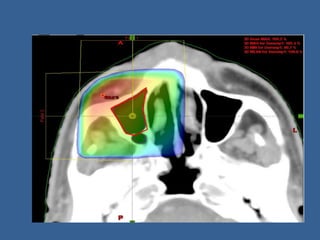

Multi leaf collimators

• Large number of collimating blocks or leaves

that can be driven automatically independent

of each other to generate a field of any shape.

• Typical MLC consists of 80 leaves or more

Advantages of Multi leaf collimators

• 1.beam shaping is simple and less time

consuming.

• 2. can be used without entering treatment room.

• 3.correction and changing of field shape is simple.

• 4.overall treatment time shortened.

• 5.constant control and continuous adjustment of

the field shape during irradiation in advanced

conformal radiotherapy is possible

• Eliminates the use of blocks for shielding and

field shaping.

• Ideal for treating multiple number of fields.

• Integral part of newer techniques like conformal

therapy and IMRT.

Wedge Filters